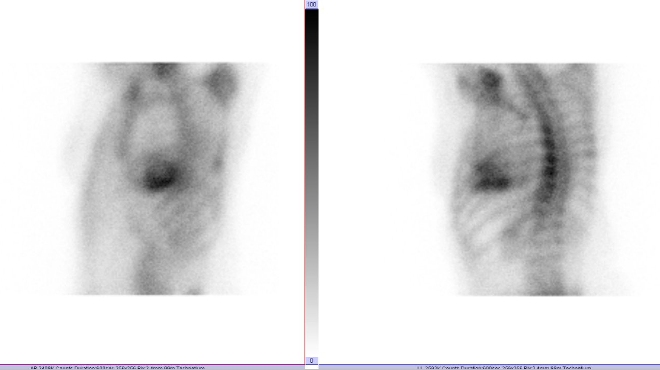

/ Obr. č. 1: Statická scintigrafie hrudníku v přední a levé boční projekci. Vyšetření 3 hodiny po aplikaci radiofarmaka.

/ Obr. č. 2: Tomografická scintigrafie myokardu. /

Prokazujeme zvýšenou depozici radiofarmaka v myokardu levé srdeční komory. Zvýšená depozice je vyšší než v žebrech - dle semikvantitavní škály jde o stupeň 3.

Vyšetřením potvrzujeme transthyretinovou srdeční amyloidózu.